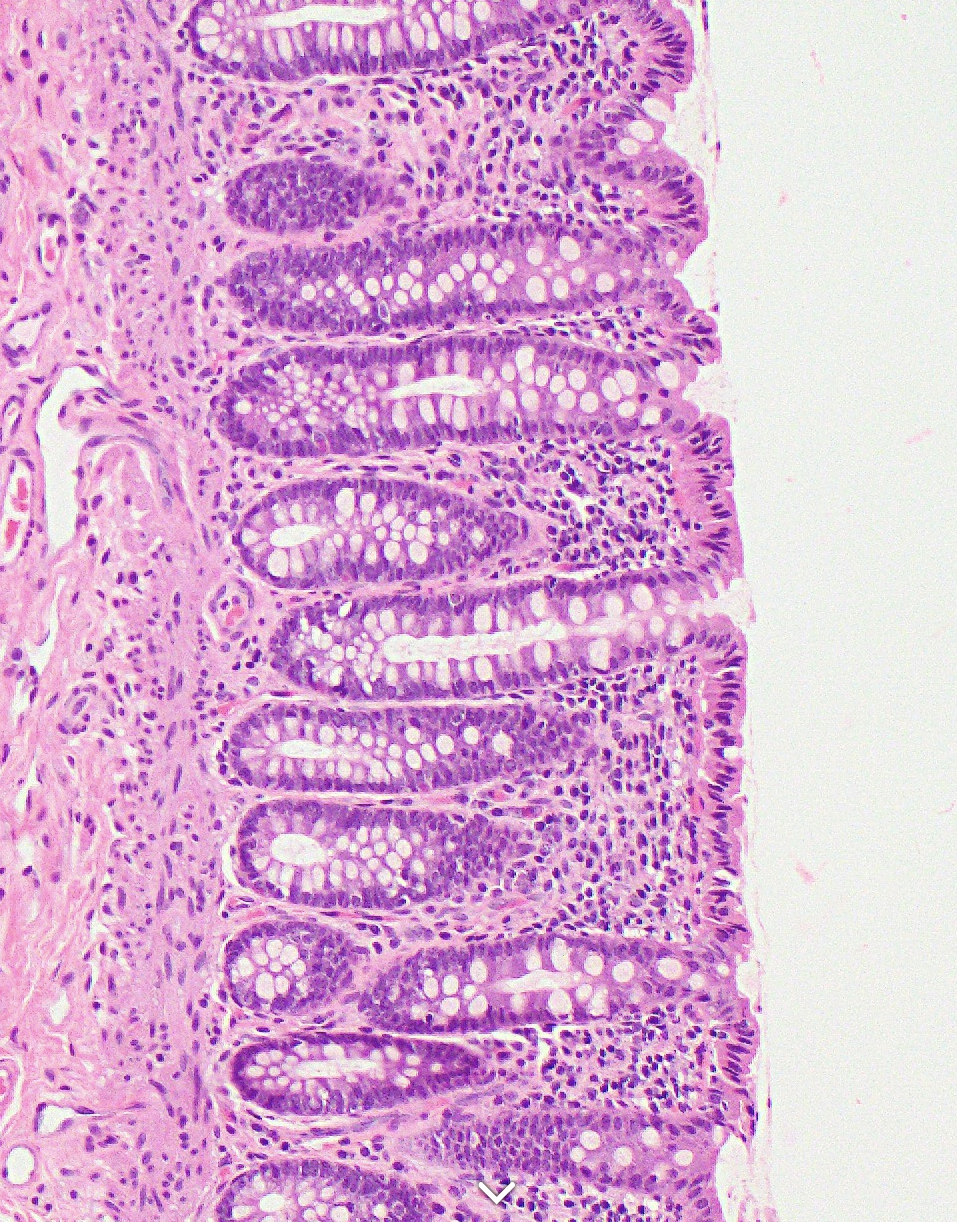

Image showing colonic mucosa, from https://www.pathologyoutlines.com/topic/colonhistology.html

A big advantage of these spatial methods is that you will generally also have H&E or immunofluorescence(IF) (with cell/membrane stains or a full panel) images (and sometimes both), because now you can see the cell.

In imaging data, the ground truth for cell phenotype labels is the morphology of the cell. Even in H&Es, a pathologist can tell the difference between the different white blood cells (lymphocytes, basophils, eosinophils, neutrophils, macrophages etc.). With immunofluoresence, you lose some of this morphology but you gain the additional info of staining patterns - it is a huge advantage to learn how your protein stains are supposed to look and to tell the difference between real signal and noise or non-specific staining. Asking a pathologist who specialises in the tissue you are researching is a huge help when it comes to checking your work!

Of course, the limitations of morphology is that you can’t really tell if it’s a CD4 T cell or CD8 T cell for example, but you should also be able to recognise that if your protein CD4 signal is exclusively in the nucleus, your tissue has problems (fixation? degradation?) and this is not actually a CD4 T cell even if the measured value of CD4 is very high.

Even if we don’t use that directly in the celltype labelling, we can validate our results. We might be fairly confident on some celltypes, however if there’s one that’s giving mixed signals, it can be very helpful to inspect. Sometimes, you notice it’s a mixed cluster, or else two cell populations that are very mixed together and the signals are getting confused. This can help tease the two populations apart. You may find that its clearer to work by by plotting the cell phenotype assignments on the images than on a UMAP.